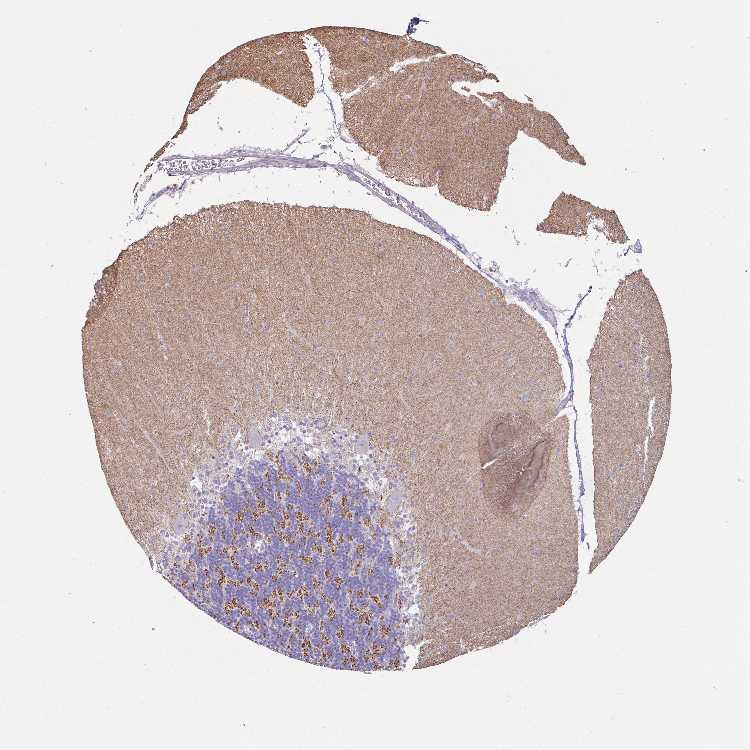

BRAIN CEREBELLUM Show tissue menu

CEREBELLUM - Antibody stainingi

Antibody staining in the annotated cell types in the current human tissue is reported as not detected, low, medium, or high, based on conventional immunohistochemistry profiling in selected tissues. This score is based on the combination of the staining intensity and fraction of stained cells.

Each image is clickable and will lead to virtual microscopy that enables deeper exploration of all samples and also displays staining intensity scores, fraction scores and subcellular localization as well as patient and tissue information for each sample.

Antibody HPA052122

Purkinje cells Not detected

Cells in granular layer Not detected

Cells in molecular layer Not detected